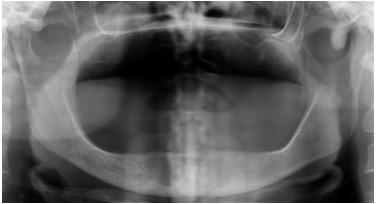

Osteoma is a benign slow-growing osteogenic neoplasm commonly occurring in the craniofacial skeleton, characterized by the proliferation of compact and/or cancellous bone. Osteomas may be peripheral, central, or extraskeletal. Peripheral osteomas arise from the periosteum and are quite uncommon in the jaw bones. The exact aetiology and pathogenesis of peripheral osteoma are unknown. Clinically, peripheral osteomas are usually asymptomatic, but depending on the location and size of the lesion, it may cause swelling, pain, esthetic disfigurement and functional impairment. On radiological imaging, a peripheral osteoma appears often as well-circumscribed, round to oval, pedunculated radiopaque mass attached to the cortex by a broad base or a pedicle. Asymptomatic osteomas are treated conservatively, while surgical excision is indicated when the lesion is symptomatic, actively growing, or for cosmetic reasons. Histologically, osteomas are composed of a normal-appearing, dense mass of lamellar bone. Recurrence of peripheral osteoma after surgical removal is extremely rare and there are no reports of malignant transformation. A review of the literature disclosed only 7 well-documented cases of peripheral osteoma located at the zygomatic bone. The purpose of this article is to present the clinical, radiographic, surgical and histological features of a solitary peripheral osteoma of the left zygomatic arch in a 55-year-old woman and to review the literature about this uncommon pathologic entity.

骨瘤是一种常见于颅面骨骼的良性、生长缓慢的成骨性肿瘤,其特征是密质骨和/或松质骨增生。骨瘤可分为外周型、中心型或骨外型。外周型骨瘤起源于骨膜,在颌骨中较为罕见。外周型骨瘤的确切病因和发病机制尚不清楚。临床上,外周型骨瘤通常无症状,但根据病变的位置和大小,可能会引起肿胀、疼痛、美观受损和功能障碍。在放射影像学上,外周型骨瘤通常表现为边界清晰、圆形至椭圆形、带蒂的不透射线肿块,通过宽基底或蒂附着于皮质。无症状的骨瘤采用保守治疗,而当病变有症状、生长活跃或出于美容原因时,则需手术切除。组织学上,骨瘤由外观正常的致密板层骨组成。外周型骨瘤手术切除后复发极为罕见,也没有恶变的报道。文献综述仅发现7例记录完整的位于颧骨的外周型骨瘤病例。本文旨在介绍一名55岁女性左颧弓孤立性外周型骨瘤的临床、影像学、手术和组织学特征,并回顾有关这种罕见病理实体的文献。